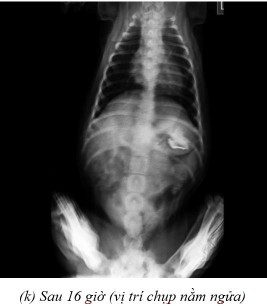

Phụ lục 5.4. Hình ảnh X-quang chó 5 ở thời điểm (a) sau 2 giờ 20 ở vị trí nằm nghiêng, (b) sau 4 giờ ở vị trí nằm ngửa, (c) sau 4 giờ ở vị trí nằm nghiêng, (d) sau 7 giờ ở vị trí nằm ngửa, (e) sau 7 giờ ở vị trí nằm nghiêng, (f) sau 9 giờ ở vị trí nằm ngửa, (g) sau 9 giờ ở vị trí nằm nghiêng, (h) sau 11 giờ 40 ở vị trí nằm ngửa và (i) sau 11 giờ 40 ở vị trí nằm nghiêng